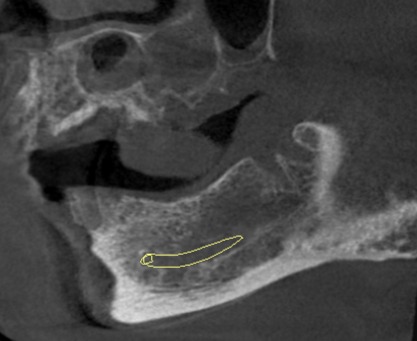

Sagittal image showing unilocular, cystic lesion with well defined periphery i.r.t distal root of carious 36. Periapical osteolysis noted with mesial root. Loss of lamina dura is noted with both roots of 36 and mesial root of 37 (yellow marker).